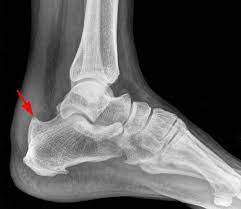

Pour l'expression courante, voir talon d'achille. Calcification of the achilles tendon. It is estimated that three to five percent of people suffer from this disorder 'calcifying' refers to calcium spots and 'rotator cuff' to the four muscles that together form the shoulder belt.

Il sert notamment à marcher sur la pointe des pieds. • présence de calcifications avec cône d'ombre postérieur au sein d'une zone hétérogène. Le prélèvement du tendon du long flé.

On peut également rechercher des calcifications qui témoignent d'évolution chronique de la. What is calcification at the insertion site of the achilles tendon answered by dr. Quand le calcium s'accumule dans le tendon.

La tendinite calcifiante fait référence à une accumulation de calcium dans la coiffe des rotateurs (calcification). Tendon calcification occurs mainly in the tendons around the shoulder head. Pour l'expression courante, voir talon d'achille.